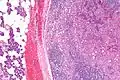

| Micrograph of an acinic cell carcinoma (right of image) and acinar glands (parotid gland - left of image). H&E stain. | |

Basophilic, bland cells similar to acinar cells. Growth pattern: solid - acinar cells, microcytic - small cystic spaces mucinous or eosinophilic, papillary-cystic - large cystic lined by epithelium, follicular - similar to thyroid tissue.